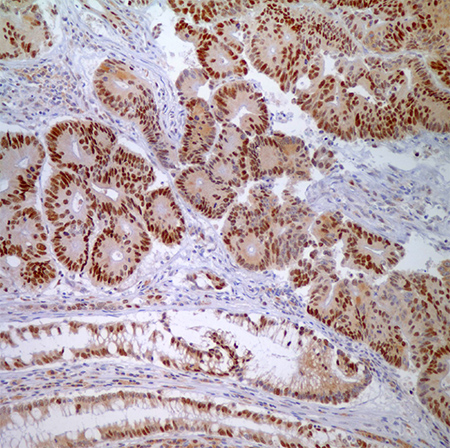

图 4.腺癌细胞与正常隐窝上皮细胞MSH6 (44)-核酸标记。

大多数的诊断解剖病例实验室都很容易进行IHC检测。可以购买到LS相关的4个蛋白抗体(通过相关基因的种系突变)。一类不正常的结果是一个或多个肿瘤中的蛋白核免疫反应活性完全缺失。所有4个蛋白在非肿瘤组织中正常表达。因此,间质、淋巴细胞和非肿瘤性隐窝是重要的内参。抗原回收步骤是很重要的;在一项研究中,不充分的抗原回收和染色不够以及LS低特异性有关(然而高背景染色会导致低灵敏度)。98染色不够和异质染色经常发生,这可能是组织固定不均匀或其他技术因素造成的。在这些案例中,重复进行IHC可能有帮助。在林奇筛查中使用IHC的一个关键优势是它能够指导基因测试。MSH2功能丧失(因为缺失突变),MSH2和MSH6的免疫组织化学(IHC)不表达;而如果是MLH1功能丧失(因为缺失突变或启动子过度甲基化),就会出现MLH1和PMS2免疫组织化学不表达。单纯的MSH6或PMS2蛋白缺失说明对应各自基因发生了突变。